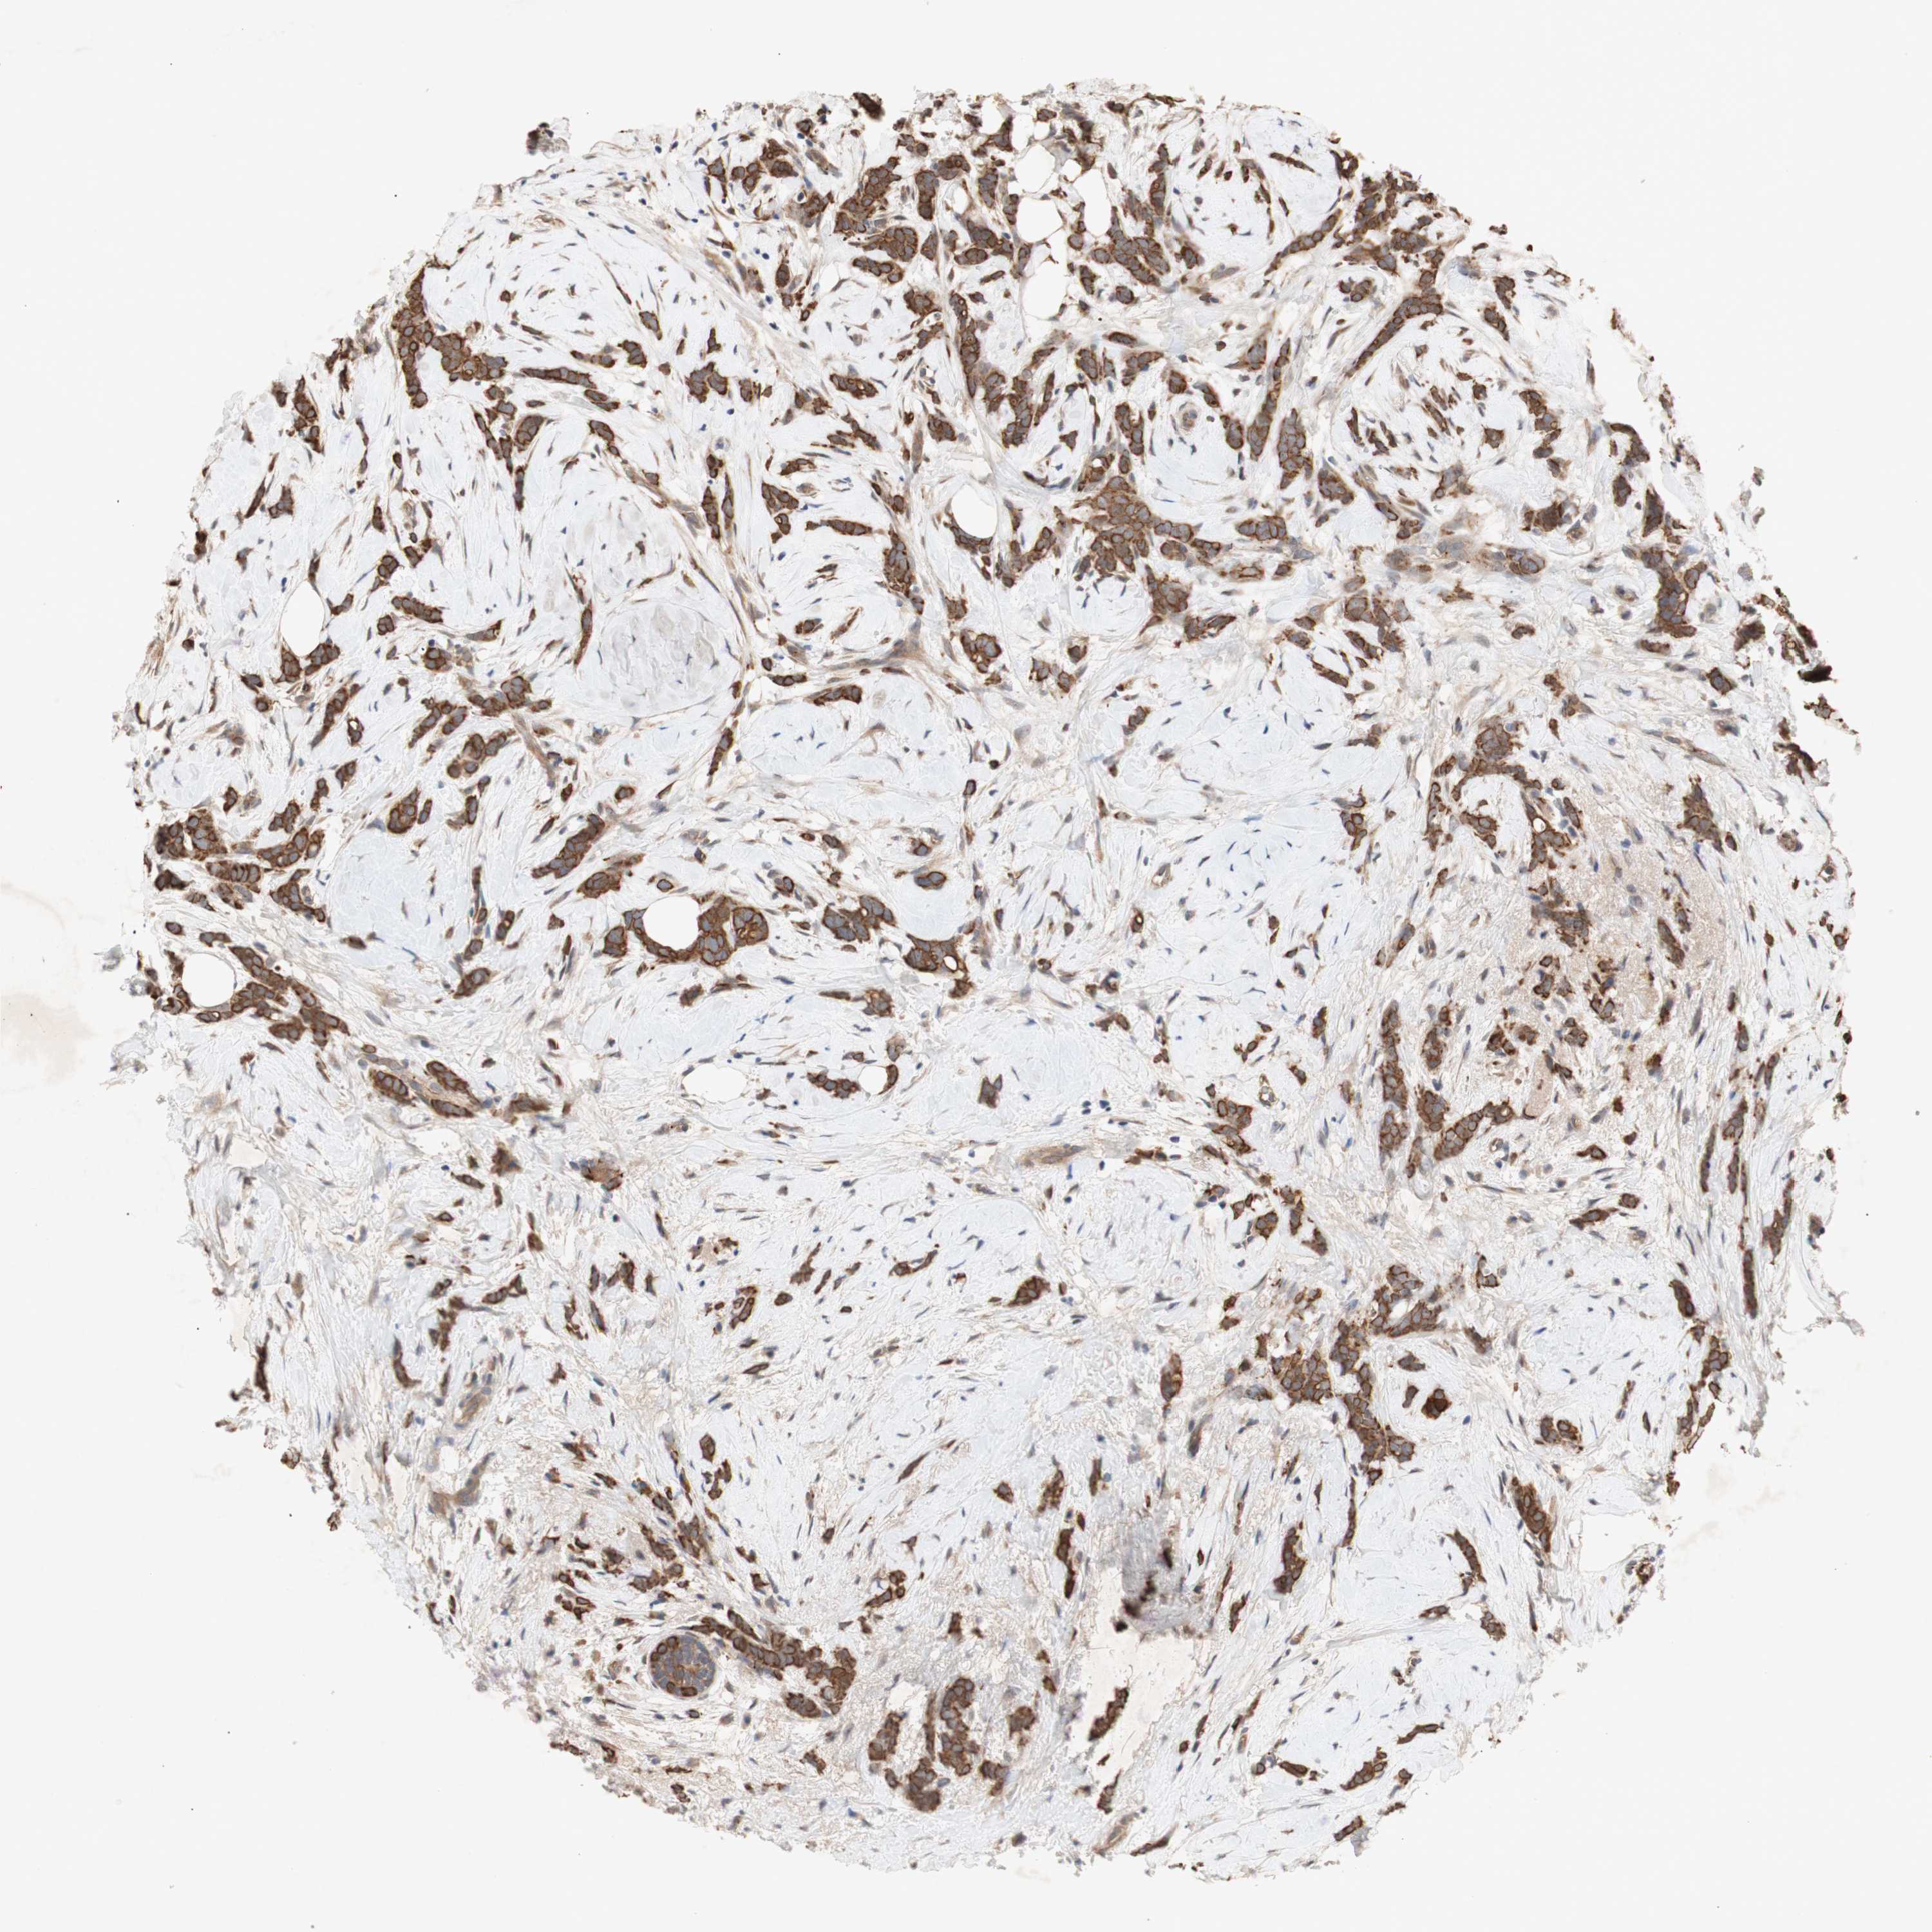

CANCER BREAST CANCER Show tissue menu

BRCA TCGA BRCA VALIDATION PROTEIN EXPRESSION

ANTIBODIES

AND

VALIDATION